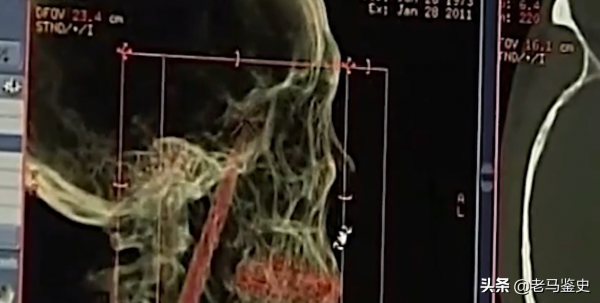

經過這次的掃描福元腦中的金屬異物終於露出了真面目,竟然是一把刀。

這樣的情況讓福元和家人無比崩潰,一把10釐米的刀,讓他們害怕至極。

腦中藏刀這是誰也不敢想象的,一個人的頭顱從左到右也不過20釐米,而福元腦袋中這把刀長達10釐米,相當於貫穿了人的半個腦袋。

現在刀的位置分別在福元腦袋當中的三個位置,

刀尖的部分靠近顱頂,中間部分因為位移暴露在口腔、鼻咽的部位,底部則在舌根的位置。